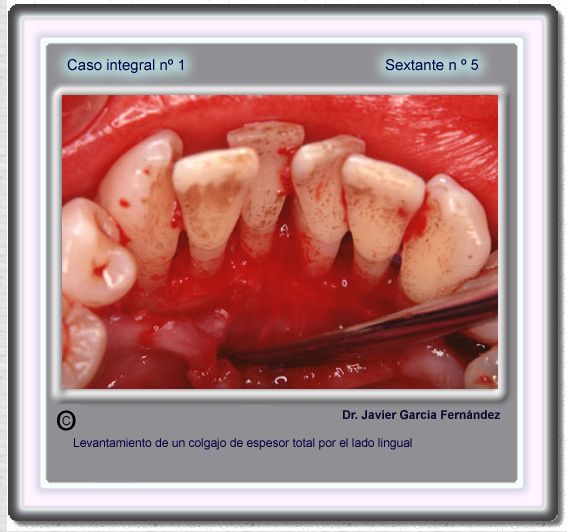

image 86